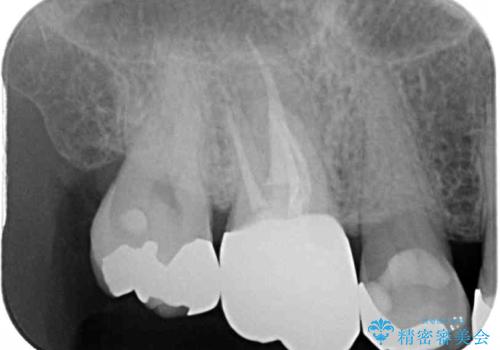

根管治療後には痛みが引き、半年後のレントゲンからは根尖部の病変が縮小している様子が分かりました。

咬んだときの感触も良好で、患者様には大変満足していただきました。